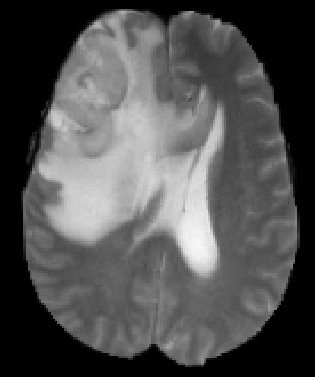

(a) Input images (b) Semantic Labels (c) Seg-Net+EG-CNN (d) Seg-Net

We argue that the sub-optimal paradigm of processing different abstractions within a single CNN pipeline can be remedied through the effective processing of information in a structured manner. Consequently, we devise strategies for disentangling the edge and texture information within a single training pipeline. Figure 2 illustrates how our proposed module, dubbed EG-CNN, can be paired with any existing CNN encoder-decoder to improve segmentation quality near intensity edges. We have applied our EG-CNN to the tasks of brain and liver tumor segmentation in medical images (Figure 3).